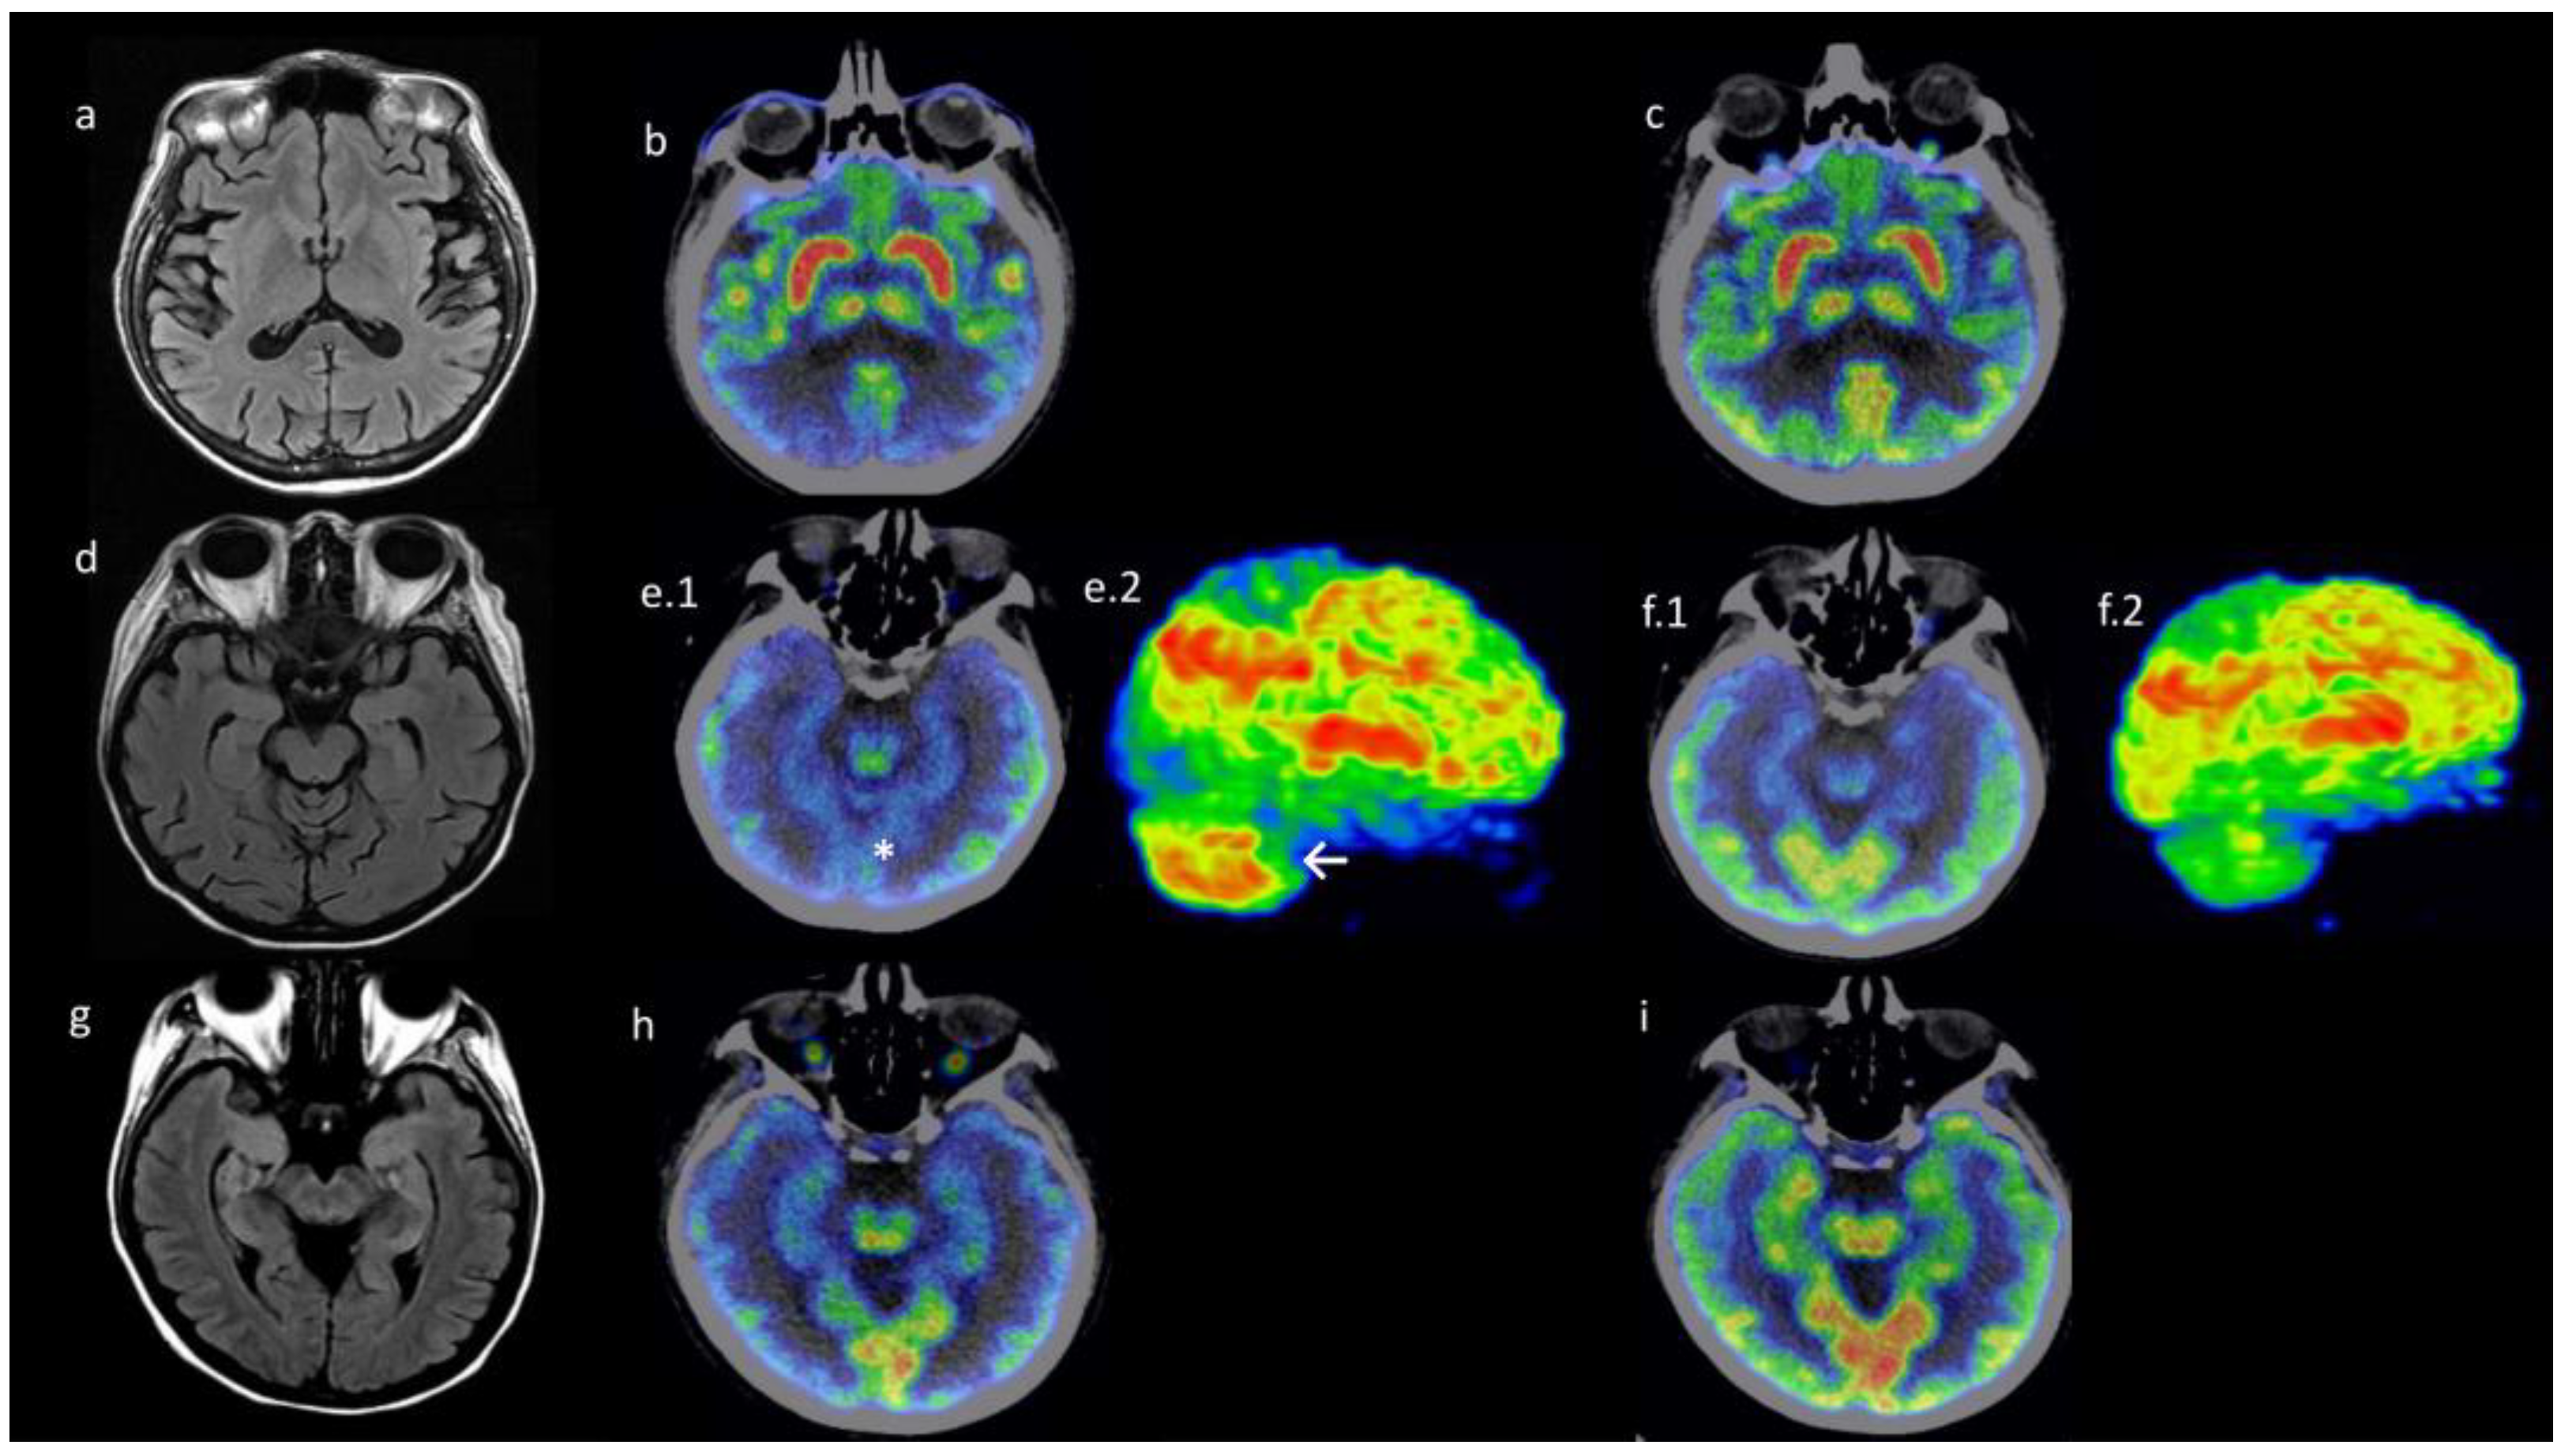

3.3. Neuroimaging Findings: Patients with Dermatomyositis-Related Encephalopathy Had Differential Metabolism Pattern in PET/CT Images